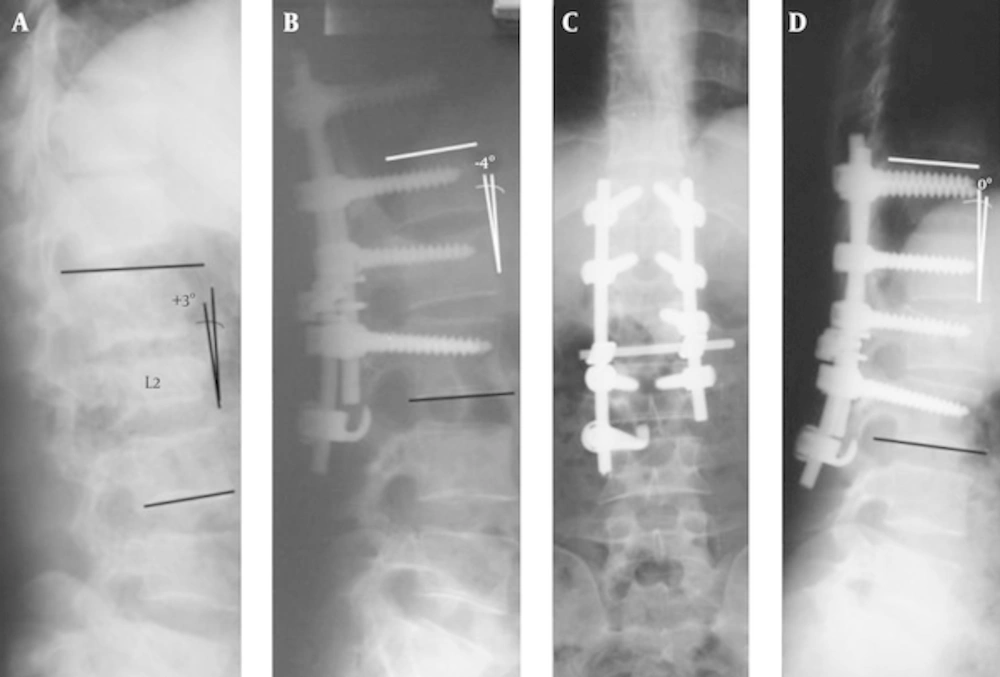

In all of the patients, primary closed reduction before skin incision was carried out by gentle trunk hyperextension while the patient placed in prone position. Gentle intraoperative distraction and regional lordosis restoration were also performed. In this modified technique, we instrumented two intact upper vertebrae but spared one intact lower lumbar vertebra with inserting one pedicular screw into the fractured vertebra and adding one contralateral infralaminar hook at the intact inferior adjacent vertebra (Figure 1). We used neither laminectomy nor direct fracture reduction in this study. Transverse connectors were uniformly added at the level of the fractured vertebra in all the cases. Postoperatively, the patients were ambulated as soon as possible (usually one or two days after surgery) while worn a soft thoracolumbar orthosis for added support. The patients usually discharged from the hospital on the day 2 or 3, after they were able to walk and void independently. They were followed-up postoperatively at 4 weeks, 3, 6, 12, and 24 months with careful clinical and radiological assessment. All significant intra- and postoperative complications were also recorded. Computed tomography was not used routinely except in the patients with suspicious pseudoarthrosis or screw malpositioning. At the most recent follow-up visit, patients’ satisfaction with surgery was assessed according to criteria derived from the North American spine society low back outcome instrument and rated as excellent, good, fair, or poor [22].

A, a 29 years old woman with L2 burst fracture, on Primary radiography; B, significant vertebral body collapse was observed due to three columns failure, significant height restoration was achieved on immediate postoperative view; C and D, remained relatively constant throughout the follow-up period of 41 months